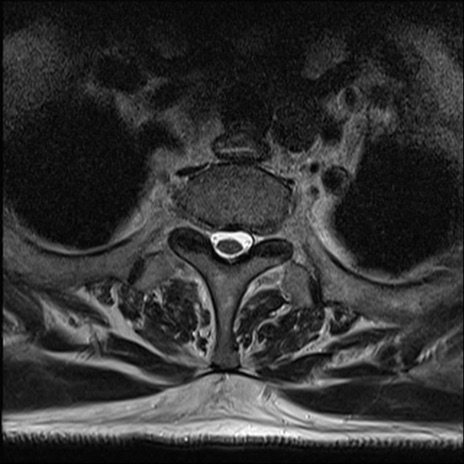

【整形】TIPS症例7 頚椎MRI T2WI(横断像)

頚椎MRI

矢状断像と横断像